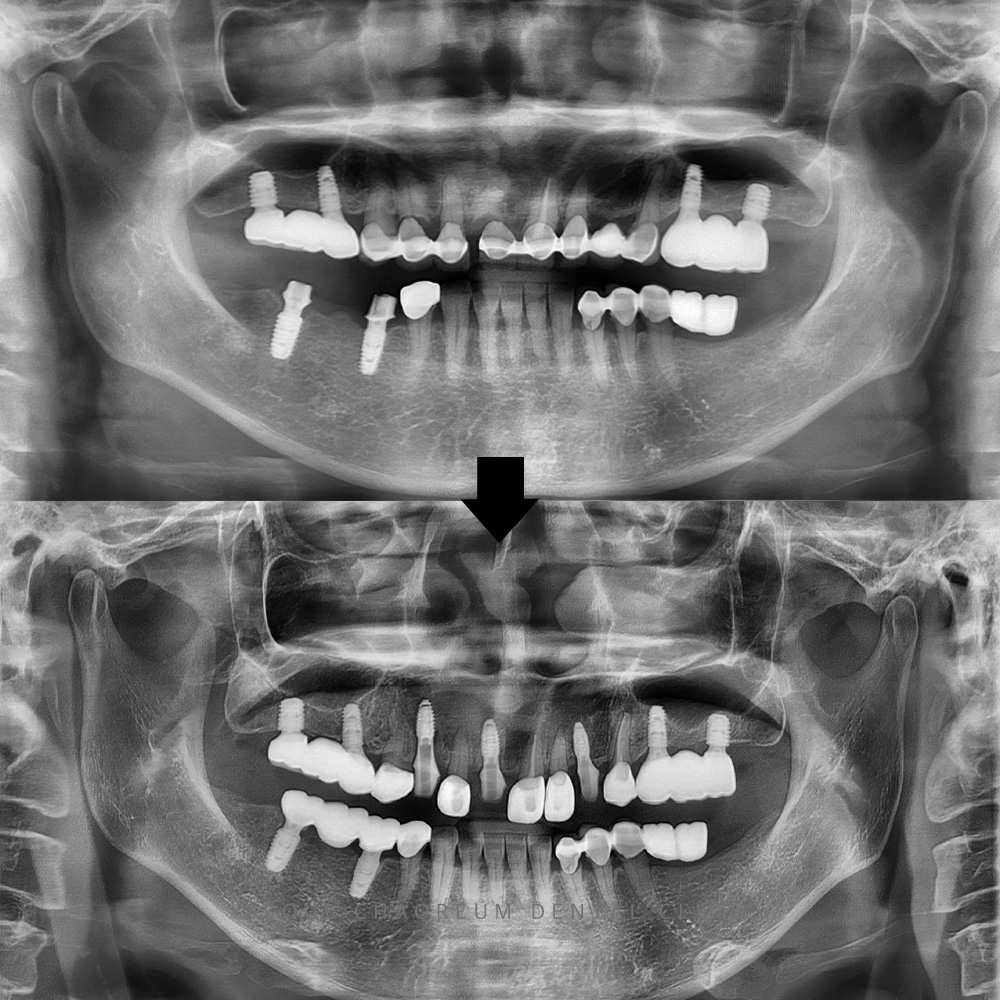

병점치과 전체적으로 임플란트 희망해요 치아가 상실된 상태로 오래 방치되면 주변 치아들이 빈 공간으로 쓰러지거나 위·아래로 정출되는 변화가 쉽게 나타납니다. 이러한 변위는 교합 불균형을 만들고 잇몸 건강을 악화시키며, 보철·임플란트…